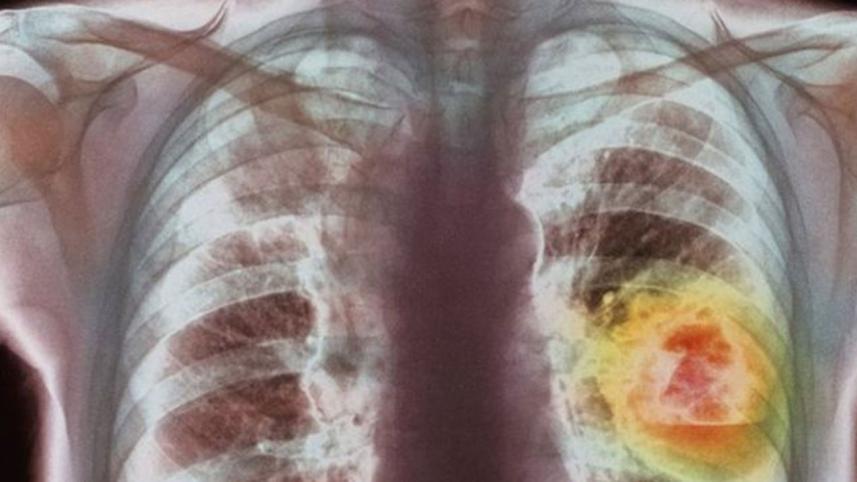

Lung cancer therapy is 'milestone'

A lung cancer therapy can more than double life expectancy in some patients, a "milestone" trial shows.

Lung cancer is the most deadly type of cancer, killing nearly 1.6 million people every year.